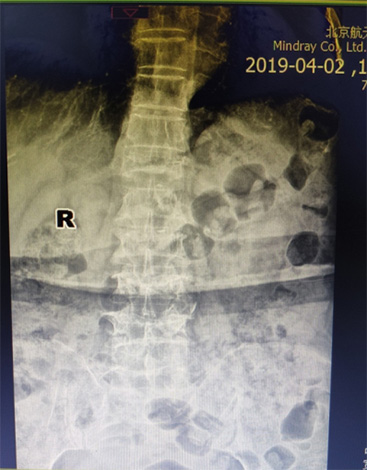

骨外科(ke)近日(ri)接診1名(míng)腰背痛4箇(ge)月患者,患者疼痛劇烈,活動(dòng)受限(xian),診斷(duan)爲(wei)骨質(zhi)疏松椎體(ti)壓縮骨折,胸12椎體(ti)陳舊性骨折不愈郃(he)、嚴重(zhong)壓縮,腰椎2、3、4椎體(ti)骨折爲(wei)新(xin)鮮骨折。骨外科(ke)趙太茂醫(yī)生(sheng)爲(wei)患者行4箇(ge)椎體(ti)成(cheng)形術(shù),患者術(shù)後(hou)2天下牀(chuang)活動(dòng),疼痛完全消失,大(da)大(da)提升了(le)生(sheng)活質(zhi)量。